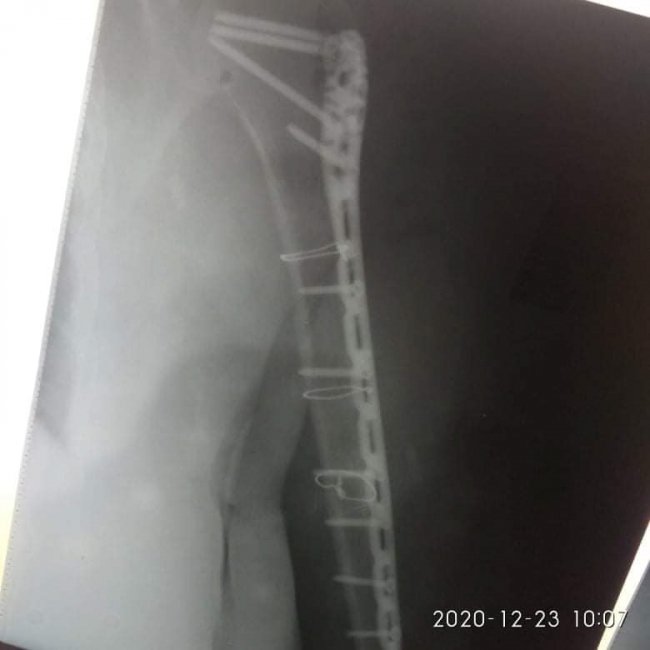

21 грудня їй провели 4-ьох годинну операцію – остеометалосинтез правої плечової кістки за допомогою LCP проксимальної Philos пластини та гвинтів.

Операція пройшла у складі лікарів-травматологів: Лотоцького І.А., Радчука В.М, Босого Т.Б..

Завдяки вчасно проведеній операції пацієнтка уже знаходиться у задовільному стані та готується до виписки.